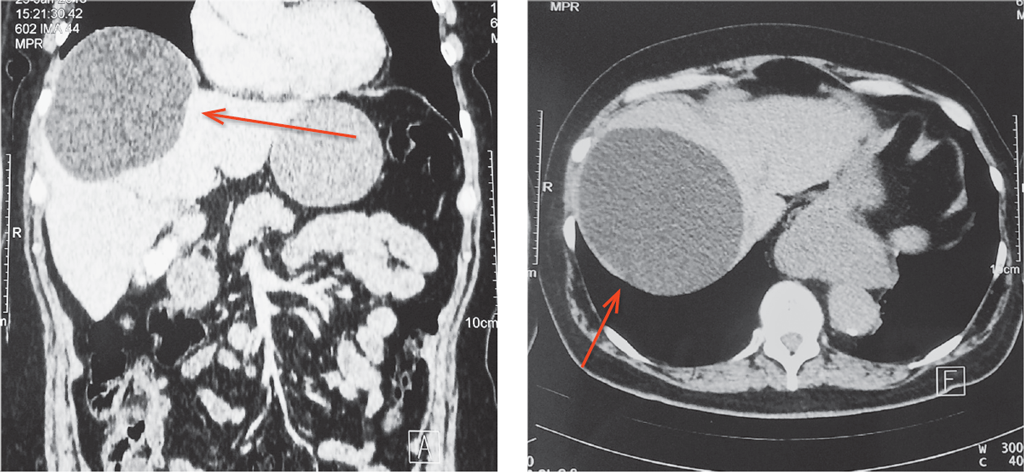

Выполнена пункция, получено около 700 мл, прозрачного экссудата (материал отправлен на бактериологическое исследование). Стенки кисты иссечены с помощью аппарата LigaSure (препарат отправлен на патогистологическое исследование). Ложе кисты обработано аргоноплазменной коагуляцией (Söring) (рис. 3). Выполнен контроль гемостаза и холестаза. Установлены дренаж в ложе желчного пузыря и два дренажа в ложе кисты.

Рис. 3. Ложе кисты после обработки аргоноплазменной коагуляцией

Fig. 3. Cyst bed after argon plasma coagulation treatment